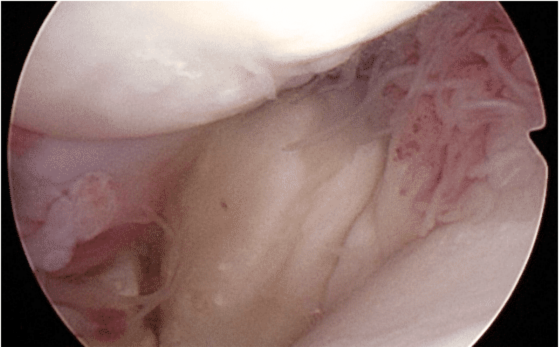

Most cases of supraspinatus tendinopathy do not have mineralization like the case above, and hence are not diagnosed with X-rays (radiographs). Most cases require use of ultrasound, MRI, or diagnostic arthroscopy for diagnostic confirmation. The arthroscopy images below show an enlarged supraspinatus tendon in a canine impinging upon the biceps tendon. The canine supraspinatus is pushing the biceps from right to left.